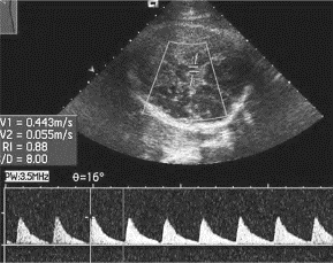

图34-8 大脑中动脉超声血流频谱